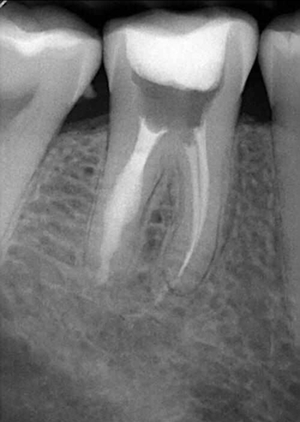

牙內吸收通常無明顯癥狀。根據(jù)吸收的類型和原因,主要分為炎癥性吸收和替代性吸收。其中,炎癥性吸收可能繼發(fā)于前期牙本質的細菌感染和創(chuàng)傷,牙本質吸收過程的進展不伴有吸收區(qū)鄰近部位硬組織的沉積,吸收部位可見大量肉芽組織,典型的影像學表現(xiàn)為,以根管為中心的橢圓形透光區(qū)。替代性吸收,導致根管內牙本質缺損的同時,在缺損區(qū)某些部位還伴有骨樣組織的沉積,造成牙髓腔不規(guī)則的擴大和根管連續(xù)性的破壞。根據(jù)牙內吸收發(fā)生部位和嚴重程度的不同,又可呈現(xiàn)不同的征象。若吸收部位發(fā)展至牙冠,可以觀察到牙冠上出現(xiàn)粉紅色的點,這是吸收細胞鄰近的結締組織高度血管化的結果。當吸收部位位于根方,則可使得根管原有的形態(tài)缺失,X線片可見根管局部氣球樣的膨大,通常邊界清晰。若牙髓還有部分的活力,則患牙可能有慢性牙髓炎的表現(xiàn);若牙髓完全壞死,則可能發(fā)展成根尖周炎,而出現(xiàn)相應的癥狀。竇道的出現(xiàn)往往是己發(fā)生慢性根尖膿腫或根管側穿的表現(xiàn)。由于患牙冠方的牙髓通常己經(jīng)壞死或被去除,因此敏感性測試常為陰性。

牙體吸收可分為生理性吸收和病理性吸收。如成熟乳牙的牙根吸收,即為一個生理性過程。病理性牙體吸收則包括牙外吸收和牙內吸收。牙外吸收的發(fā)生通常與根尖周病變、正畸治療和快速生長的腫瘤有關,始發(fā)部位為牙根外表面或牙頸部,吸收過程由外到內。而牙內吸收也被稱為髓腔內吸收,是指正常的牙髓組織肉芽變性,引起髓腔內部牙體硬組織吸收,并逐漸向周圍的牙本質層進展。如果未能得到及時的治療,將可能導致病變恒牙的早失。恒牙牙內吸收較為少見,且常無明顯臨床癥狀,多數(shù)病例為行常規(guī)影像學檢查時發(fā)現(xiàn)。然而,病變早期并無明顯影像學改變,這使得牙內吸收的早期診斷變得更加困難。因此,當患牙出現(xiàn)癥狀或者有影像學改變時,病變往往己發(fā)展至較嚴重階段,使得治療難度加大,遠期效果欠佳。[1]